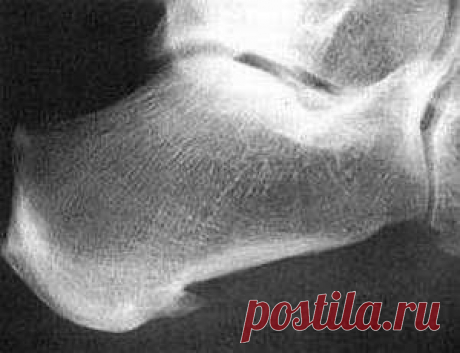

Как лечить шпору на пятке домашними методами Лечение пяточной шпоры в домашних условиях проводится с помощью компрессов, мазей, самомассажа и прогревающих ванночек. Пяточная шпора – образование костного нароста в области пятки, часто сопровождается воспалением подошвенной фасции и при этом пациента беспокоят сильные боли в пятке, шпора...